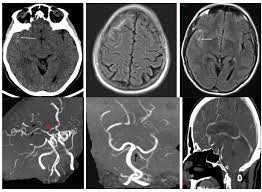

I6783 Posterior reversible encephalopathy syndrome. INTRODUCTION Reversible cerebral vasoconstriction syndrome RCVS represents a group of conditions that show reversible multifocal narrowing of the cerebral arteries with clinical manifestations that typically include thunderclap headache and sometimes include neurologic deficits related to brain edema stroke or seizure. Reversible Cerebral Vasoconstriction Syndrome RCVS is a rare cause of thunderclap headache TCH estimated cause 8-45 of TCH once aneurysmal subarachnoid hemorrhage SAH is ruled out.

Multimodal Imaging Of Reversible Cerebral Vasoconstriction Syndrome A Series Of 6 Cases American Journal Of Neuroradiology